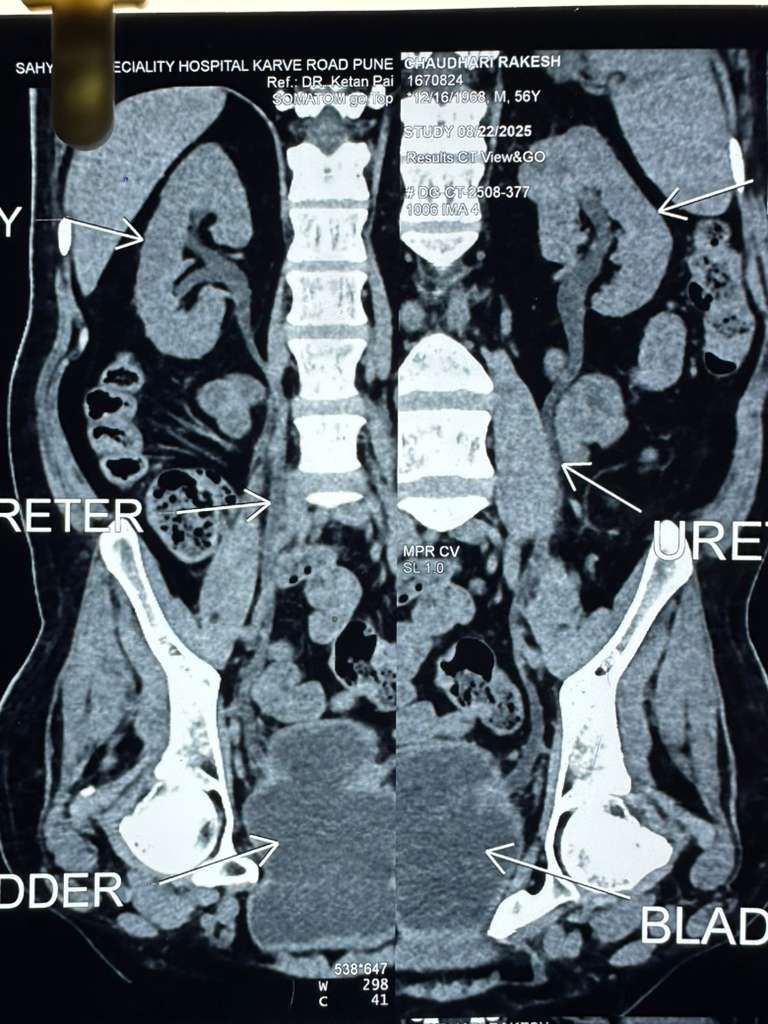

દર્દીને CECT (એબડોમન + પેલ્વિસ) એટલે કે પેટના ભાગનો સિટી સ્કેન કરાવતા આ વખતે ડાબી કિડનીના ઉપરના પોલના મધ્ય ભાગમાં 34 × 28 સાઇઝ નો કેન્સર વાળો ભાગ જોવા મળેલ. દર્દીના શરીરના અન્ય ભાગમાં કેન્સરની અસર છે કે નહીં તે જાણવા માટે ડોક્ટરો દ્વારા દર્દીનો PET- સ્કેન પણ કરાવવામાં આવ્યો હતો જેમાં સદનસીબે બીજી કોઈ જગ્યાએ કેન્સર ફેલાયું હોય કે કેન્સરની અસર હોય તેવું જણાયું ન હતું.

દર્દીના સીટી સ્કેન તેમજ પેટ સ્કેન ના રિપોર્ટો તથા દર્દીને ભૂતકાળમાં થયેલા કિડનીના કેન્સર ને ધ્યાનમાં રાખીને સિવિલ હોસ્પિટલના યુરોલોજી વિભાગના વડા ડોક્ટર શ્રેણિક શાહ અને તેમની ટીમના નિષ્ણાત ડોક્ટરો દ્વારા ખૂબ જ જટિલ એવી લૅપેરોસ્કોપિક લેફ્ટ પાર્ટિયલ નેફ્રેક્ટોમિ એટલે કે દૂરબીન થી દર્દીની કિડનીના કેન્સરની અસરવાળા ભાગ માત્રને દૂર કરવા નું સફળતાપૂર્વક ઓપરેશન કરવામા આવ્યું. એનેસ્થેસિયા dr નિલેશ સોલંકી એન્ડ ટીમ દ્વારા આપવામાં આવ્યો.. સર્જરી દરમિયાન અને સર્જરી બાદ પોસ્ટઓપરેટિવ સમય પણ કોઈપણ તકલીફ વગરનો રહેતા દર્દી ની સ્થિતિ સ્થિર જણાતા ડિસ્ચાર્જ આપી ઘરે જવા રજા આપવામાં આવી હતી